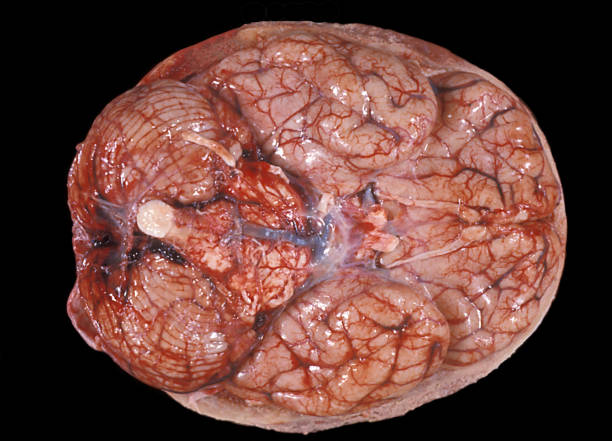

뇌 면역 체계가 완전히 발달하지 않은 영유아는 뇌수막염에 특히 취약하므로, 부모의 세심한 관찰과 적절한 예방 조치가 필요합니다. 이번 글에서는 뇌수막염의 주요 증상, 원인, 그리고 예방 방법을 의학적인 관점에서 정리해 드리겠습니다.

유아 뇌수막염의 증상은 열이 나기때문에 일반 감기나 소아 질환과 혼동될 수 있어 초기 발견이 어렵습니다. 대표적으로 고열, 잦은 구토, 심한 두통, 목의 뻣뻣함, 빛을 싫어하는 증상이 나타날 수 있으며, 생후 몇 개월 된 영아는 울음이 평소보다 심하거나, 먹는 양이 줄고, 경련을 보이는 경우도 있습니다. 또한 유아는 말을 제대로 표현하지 못하기 때문에 부모가 아이의 미세한 행동 변화까지 관찰하는 것이 중요합니다.

특히 뇌수막염은 진행 속도가 빠른 질환으로, 증상이 나타난 지 수 시간에서 하루 이내에 상태가 나빠질 수 있습니다. 의학적으로는 세균성 뇌수막염과 바이러스성 뇌수막염으로 구분되며, 세균성의 경우 생명을 위협할 수 있기 때문에 응급 진료가 필요합니다.

뇌수막염은 직접적인 뇌신경 손상, 청력 손실, 발달 지연 등의 합병증을 남길 수 있으므로 원인을 정확히 알고고 조기 예방 조치를 취하는게 중요합니다.